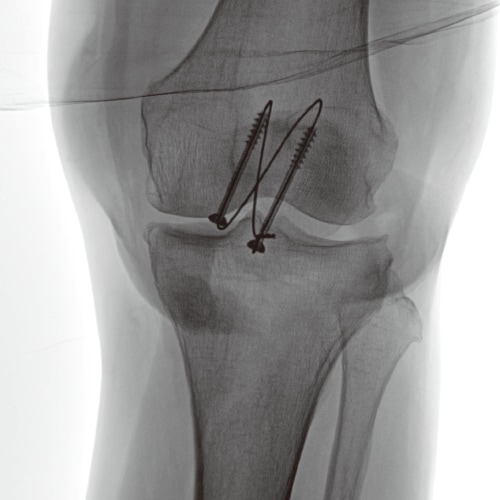

Edge enhancement

Improving procedural accuracy by enhancing the edges of bones, devices, and blood vessels without increasing radiation dose.

Original image

Low Enhancement image

High Enhancement image